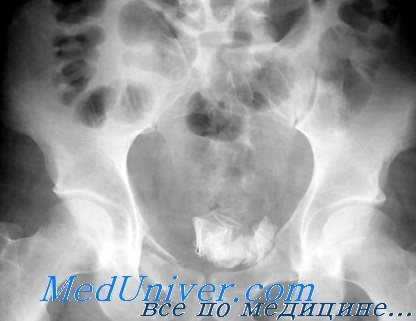

- Рентген. Ретроградная цистография считается «золотым стандартом» диагностики этого вида травм. Разрывы органа проявляются затеками рентгеноконтрастного вещества в пузырно-прямокишечную ямку, околопузырную клетчатку, область крыльев подвздошной кости, полость брюшины.